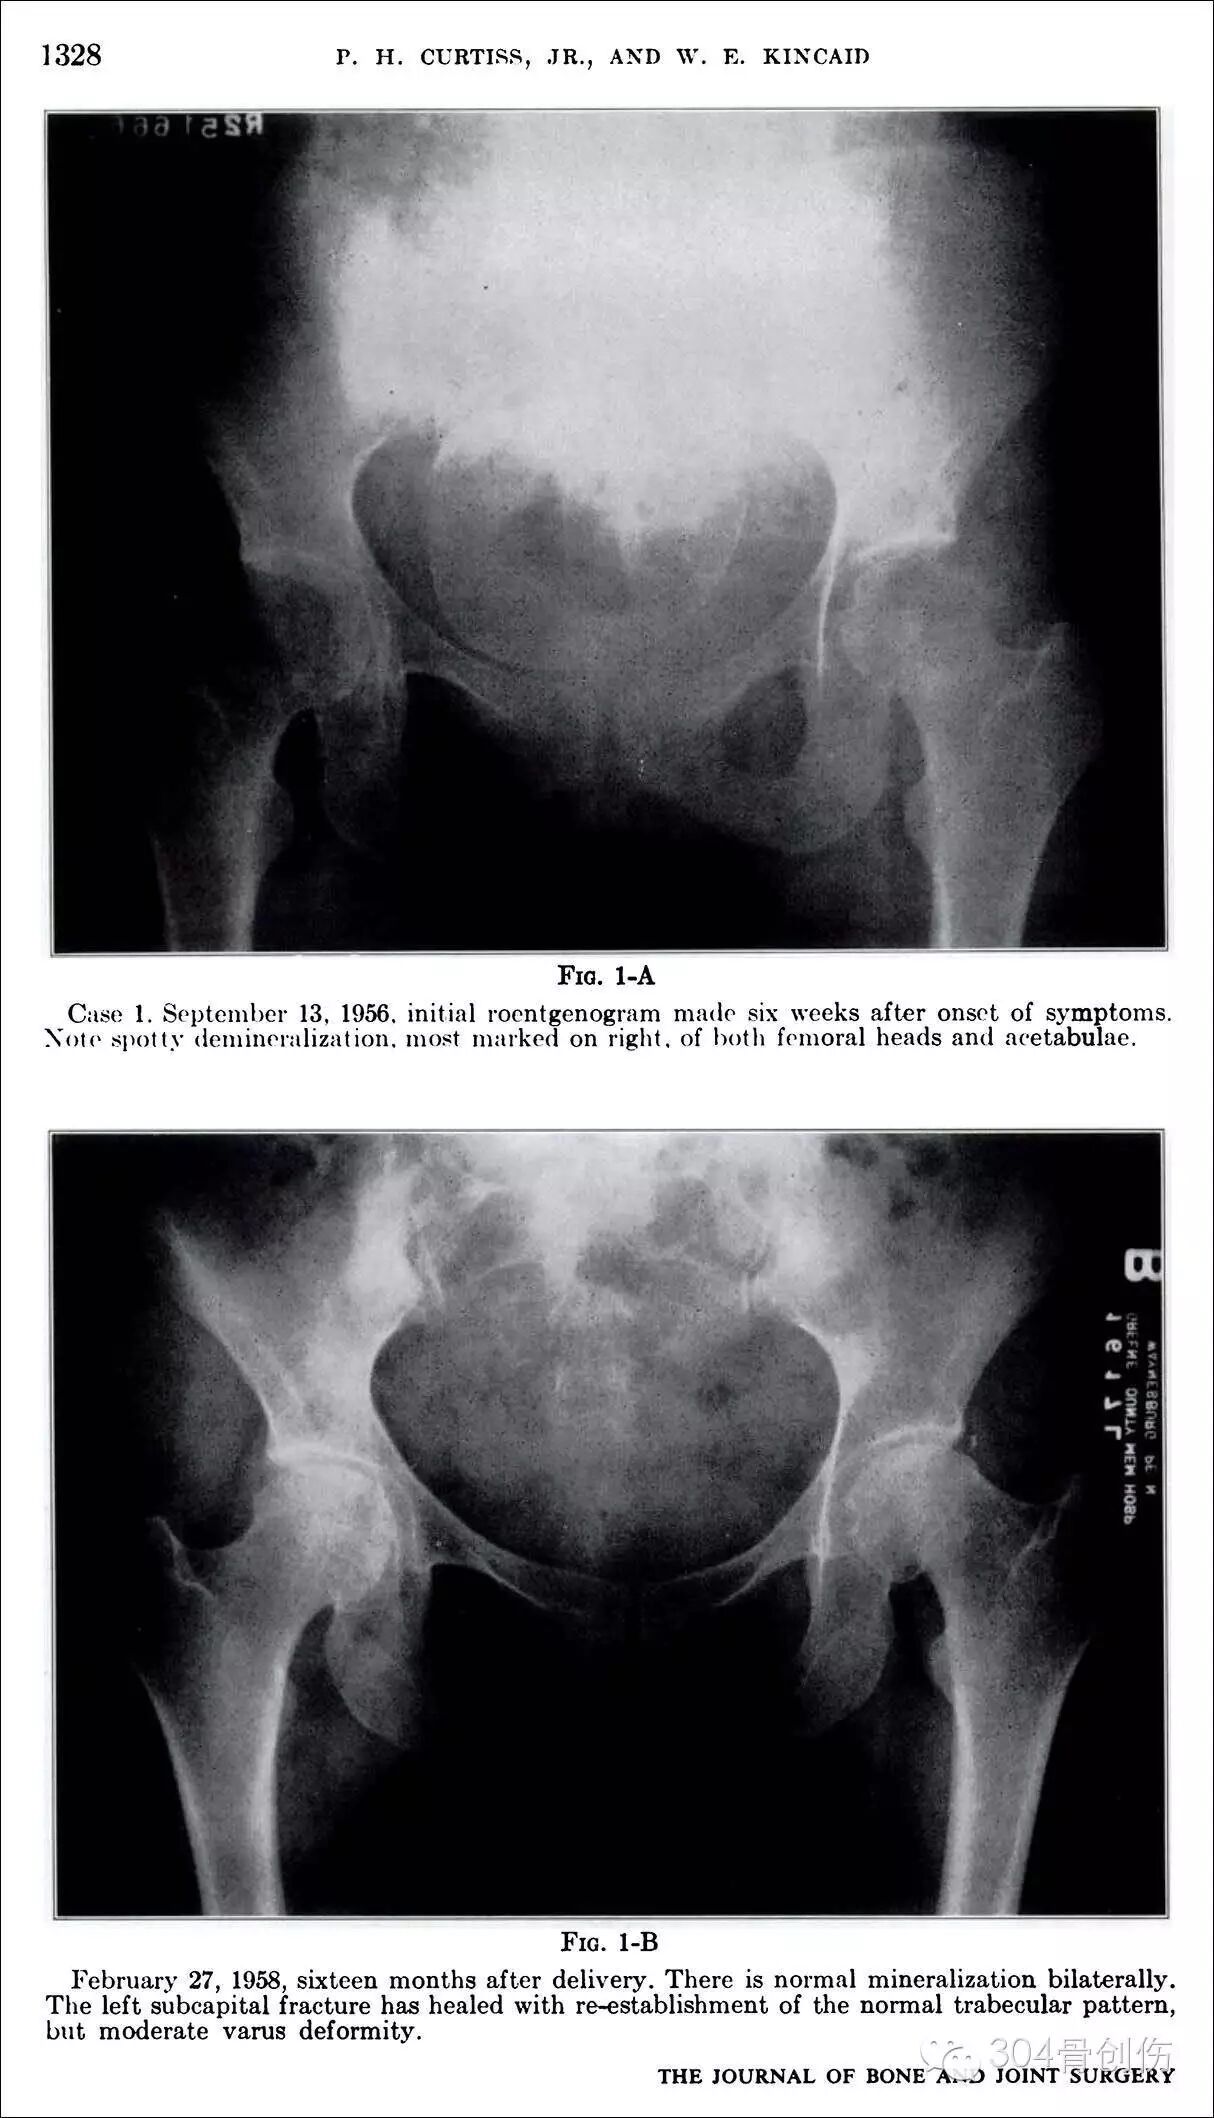

髋部一过性骨质疏松症(transient osteoporosis of the hip, TOH)是出现于妊娠晚期的一种罕见的骨代谢紊乱状况,其病因不清楚,表现为髋部疼痛及活动受限,可在髋关节X线上观察到明显骨量减少,1959年Curtiss教授首次报道(图),2005年国内郭依廷医生首次报道(图),综合发病过程,定义为“妊娠期一过性骨质疏松症”,不完全统计:全世界报道大约100余例,多为脊柱骨折,双侧股骨颈骨折少见,陈旧股骨颈骨折处理极为困难,目前缺乏大宗相关文献报道。

图-1959年Curtiss首次报道

1.Curtiss PH Jr, Kincaid WE. Transitory demineralisation of the hip in pregnancy. A report of three cases. JBJS(A),1959 ; 41: 1327~1333.